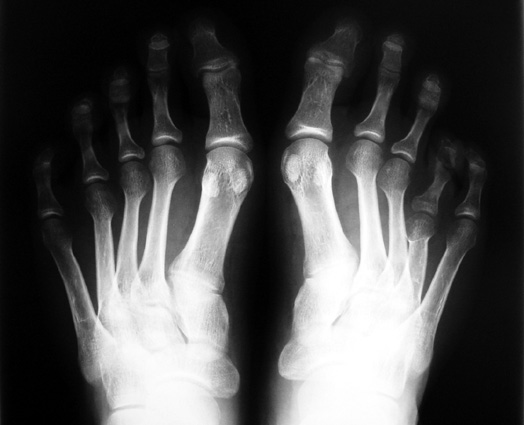

El parmağı (metakarp) ve ayak parmağı (metatars) kısalıkları doğuştan tek başına, geniş bir sendrom grubuyla birlikte, travma sonrası, Freiberg hastalığı (avasküler nekroz) sonrası görülebilir.

Doğuştan metakarp ve metatars kısalığının görülme sıklığı 1/1000’den azdır. Kadınlarda erkeklere göre 5 kat daha fazla görülür ve sıklıkla (%72) iki taraflıdır. En sık 4. parmak tutulur. Bu tür olgularda sorunun nedeni tam olarak bilinmemekle brlikte deformitenin genellikle epifiz plağının erken kapanmasından kaynaklandığı düşünülmektedir.

Metakarp kısalığında kozmetik görünümün bozulması ve dominant elin kullanımı sırasında yorulma, metatars kısalığında ise kozmetik haricinde metatarsalji, kısa parmağın dorsale kayması sonucu deformite oluşması, plantar yönde açılanması sonucu ağrı ve bası ülserleri, ve ayakkabı giymede zorluk nedeniyle ameliyat gerekebilir.

Doğuştan metakarp ve metatars kısalıklarının redavisi için pek çok teknik tanımlanmakla birlikte en çok akut uzatma sonrası kemik uçlarına greft konması ve distraksiyon osteogenezi (kallotasis) kullanılmaktadır. 1 cm.den daha fazla uzatma gereken olgularda kallotasis yöntemi önerilmektedir. Kliniğimizde de metatars ve metakarp uzatma için unilateral eksternal fiksatör ve sirküler eksternal fiksatör yardımıyla distraksiyon osteogenezi yöntemi tercih edilmektedir.